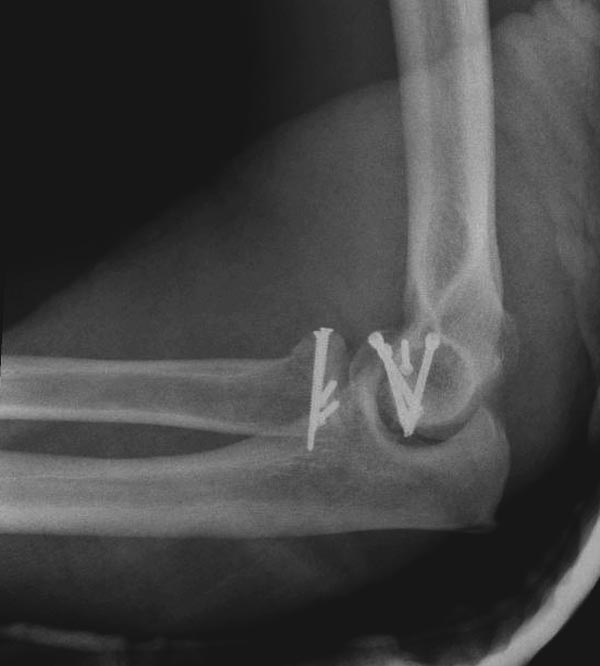

На представленных снимках есть смещение суставной поверхности. Принцип лечения внутрисуставных переломов - восстановление суставной поверхности. У нас есть опыт восстановления таких переломов микровинтами. Удачи!

Переломы по Mason первой степени без блокировки и смещение до 2х мм можно лечить в обычной косынке, или брейсом - консервативно. Перелом второй степени оперативно, а многооскольчатые переломы третьей степени лечатся заменой головки.

Популярная в странах СНГ резекция головки луча в наших условиях делается очень редко, потому что без упора луча могут проявиться симптомы нестабильности в дистальном радио-ульнарном сочленении. Реконструкция с сохранением головки дает лучший результат, но не всегда возможна.

В первом случае перелом Монтеджи, где доперационно сделано оценка положения головки к остальным элементам под рентгеном. Учитывая правильность взаимотношении произведена фиксация только локтевого отростка, Второй случай, заменена на протез, и третий, кроме фиксации головки - реконструкция capitellum латерального мыщелка.